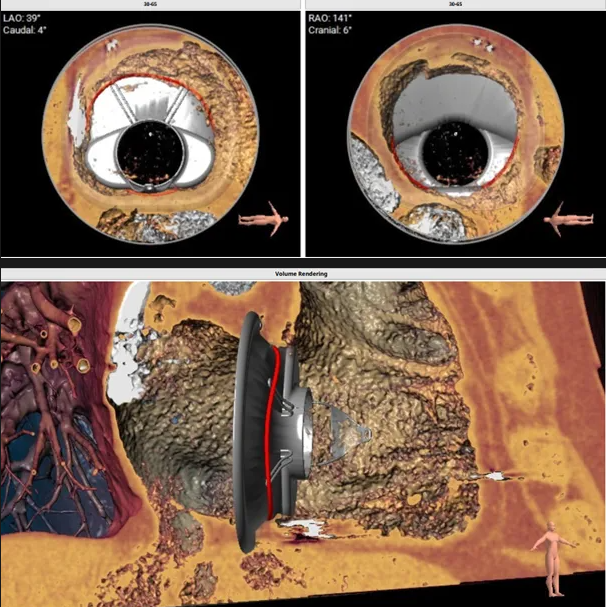

術(shù)前心臟CT評估

三尖瓣環(huán)平均周長徑58.8mm,最大直徑62.2mm

三尖瓣環(huán)切線位夾角 85°

瓣膜植入模擬